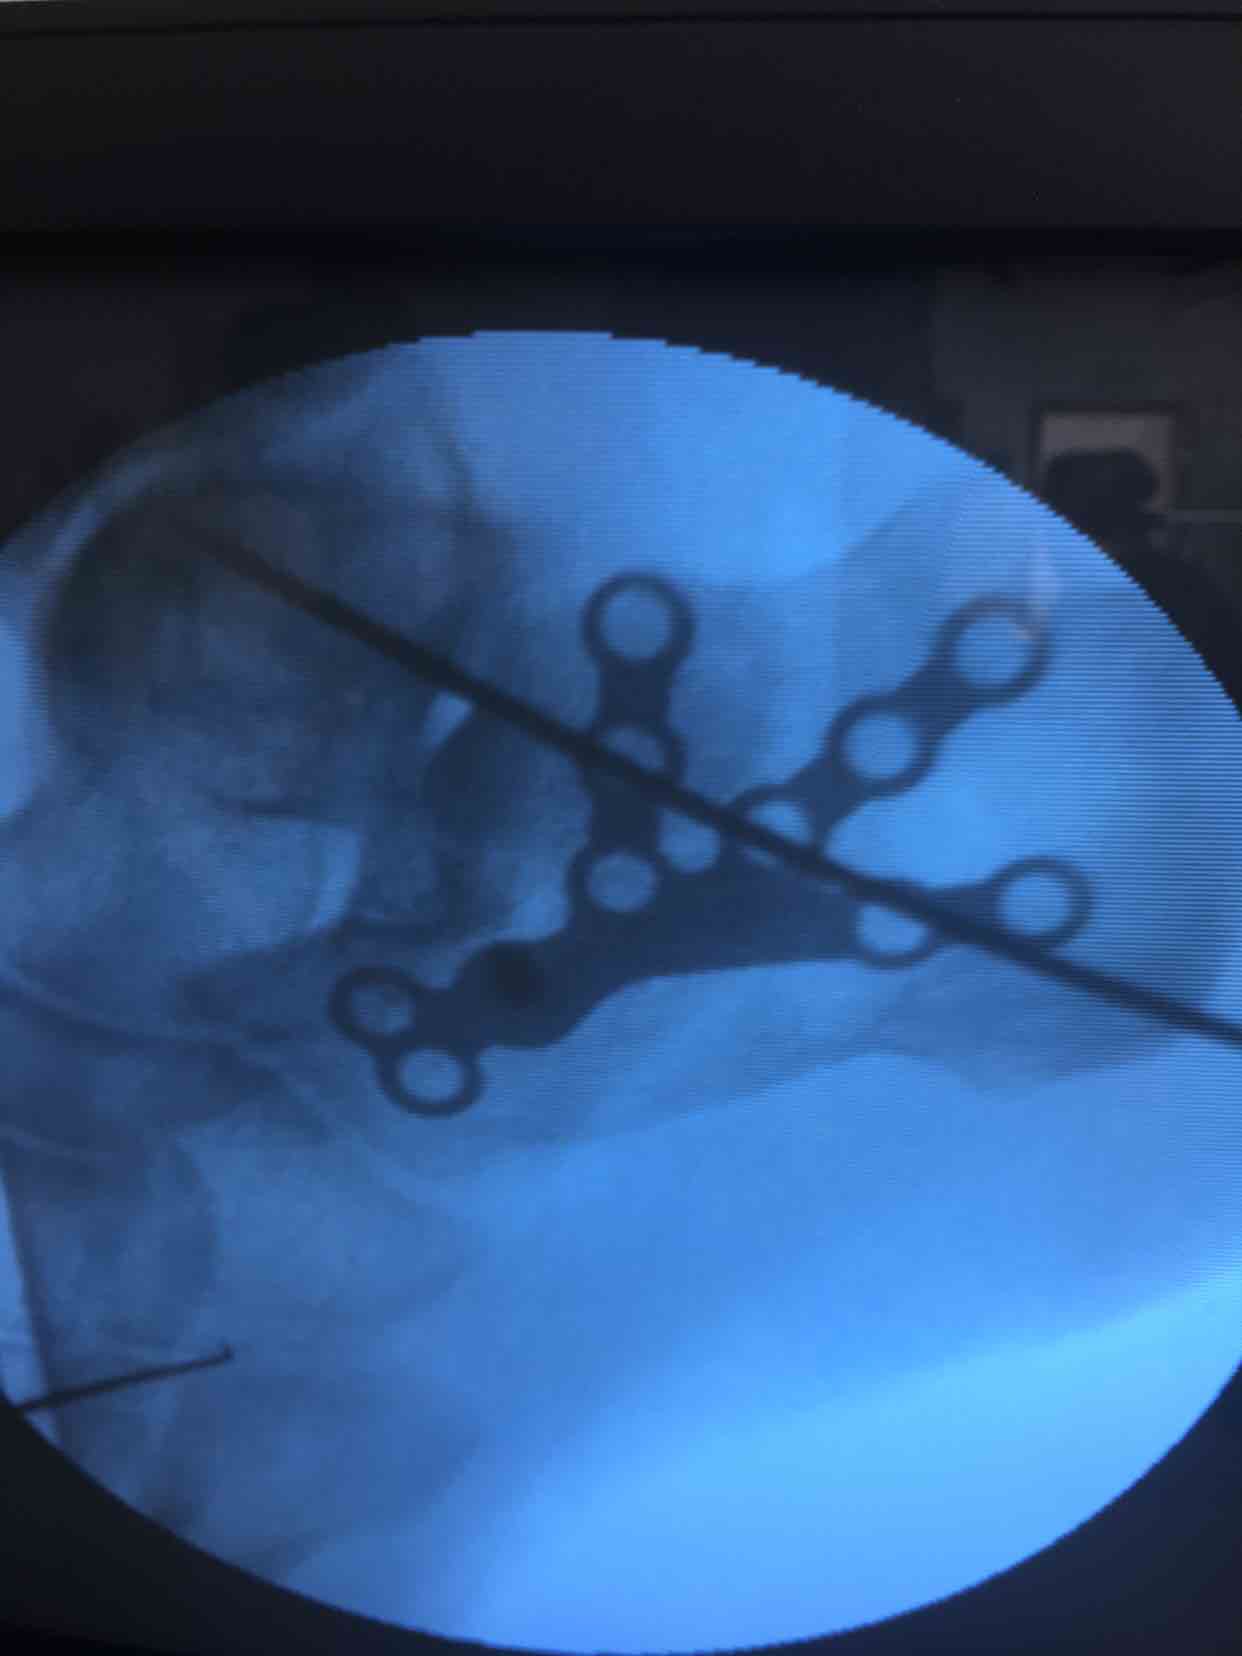

诊断  左跟骨粉碎性骨折完善术前检查,在腰麻下行切复内固定术,术中撬拨复位,选用克氏针临时固定,放置锁定钛板固定,术后抗炎,消肿等处理。